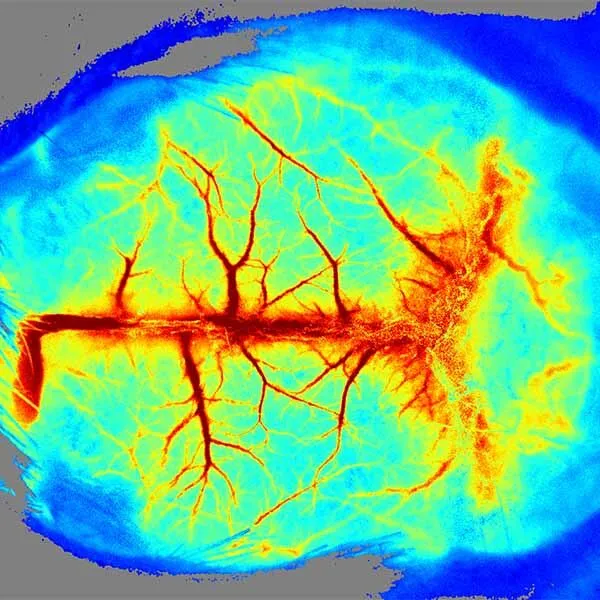

Визуализация in-vivo в ближнем ИК2 (NIR-2) диапазоне

Визуализация in-vivo в ближнем ИК2 (NIR-2) диапазоне